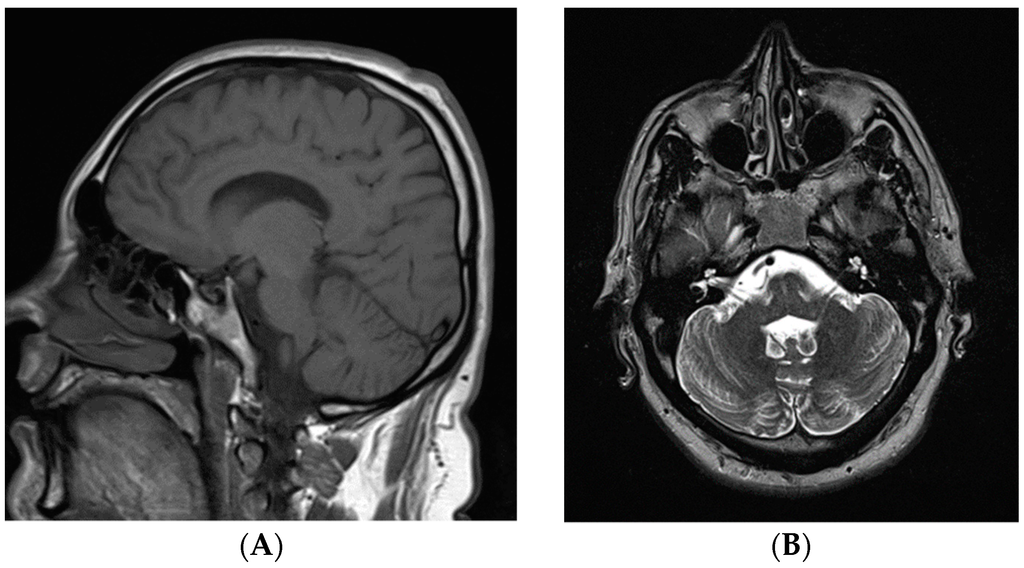

His physical examination demonstrated a high frequency of up-down action tremor without any resting tremor, truncal tremor, titubation, or extrapyramidal signs. Although he had no cerebellar signs in his limbs or nystagmus, he demonstrated a slightly wide-based gait and was unable to complete tandem gait suggesting a mild degree of cerebellar dysfunction. No other involuntary movements or pyramidal signs or apraxia were present. His brain magnetic resonance imaging revealed mild cerebellar atrophy (Figure 2).

Figure 2.

Magnetic resonance imaging of the brain. (A) T1 weighted sagittal view; and (B) T2 weighted axial view. Both images demonstrate the normal appearance of the cerebellum.